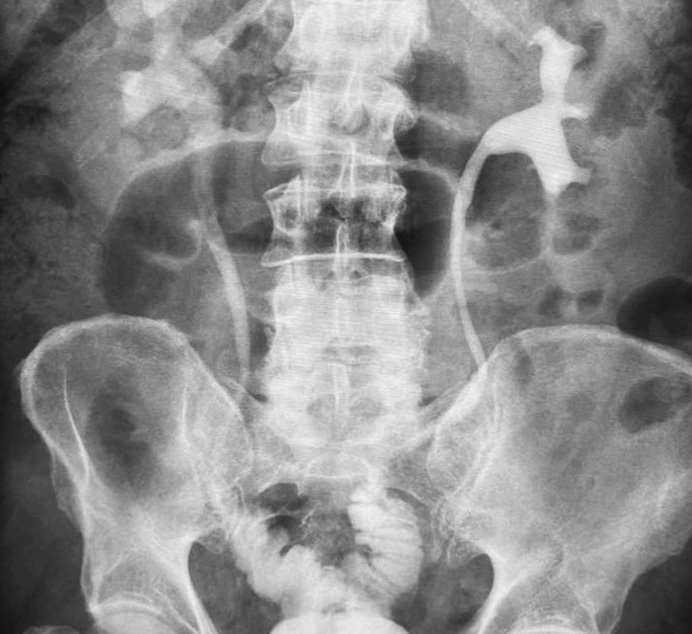

Fig. 9. Excretory ureterogram one year after laparoscopic bilateral U-shaped ileoureteroplasty. The function of the kidneys and newly created urinary tract is normal

Fig. 8. Bilateral U-shaped ileoureteroplasty

Bilateral small intestinal reconstruction of the ureters was performed in 40 (20.7%) patients. Most often, in 24 (60.0%) patients, U-shaped ileoureteroplasty was performed (Figs. 8 and 9), and more complex reconstructions were performed less often; that is, Y-shaped in 1 (2.5%) case, J-shaped in 3 (7.5%), L- and 7-shaped (Figs. 10 and 11) ileoureteroplasty in 6 (15.0%), and that with two separate ileografts in 6 (15.0%) cases.